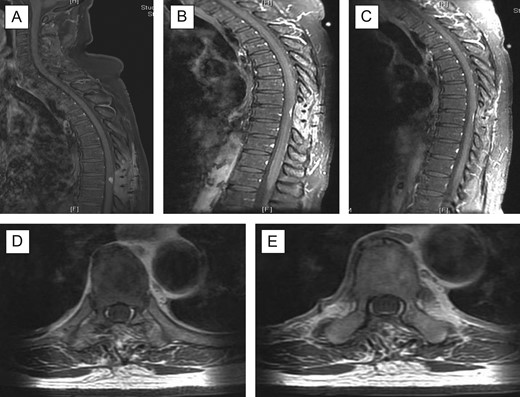

X-ray thoracolumbar spine anterior-posterior and lateral views were performed and showed slight loss of the T6 anterior vertebral height and sclerosis of the T5/T6 endplates. Mild narrowing of the T5/T6 intervertebral disc space was also seen and there were no evidence of fractures or spondylolisthesis. Magnetic resonance imaging (MRI) of the spine with contrast was then requested, showing 1.6 Ă— 1 Ă— 1.2 cm3 enhancing lesion in the spinal cord at level T9, mostly extramedullary intradural location compressing the thoracic cord with extensive cord oedema from T1 down to conus (Fig. 1). It was also suggestive of intramedullary invasion into the spinal cord, from the extramedullary enhancing mass lesion.

Pre-op MRI scan. Enhancing intraspinal lesion, most likely extramedullary intradural in location, at the level of T9 causing spinal cord compression associated with extensive cord oedema; (A) T2 sagittal; (B) with contrast, sagittal; (C, D) axial with contrast at T9 level; suggestive of intradural extramedullary (C) extending intramedullary (D).